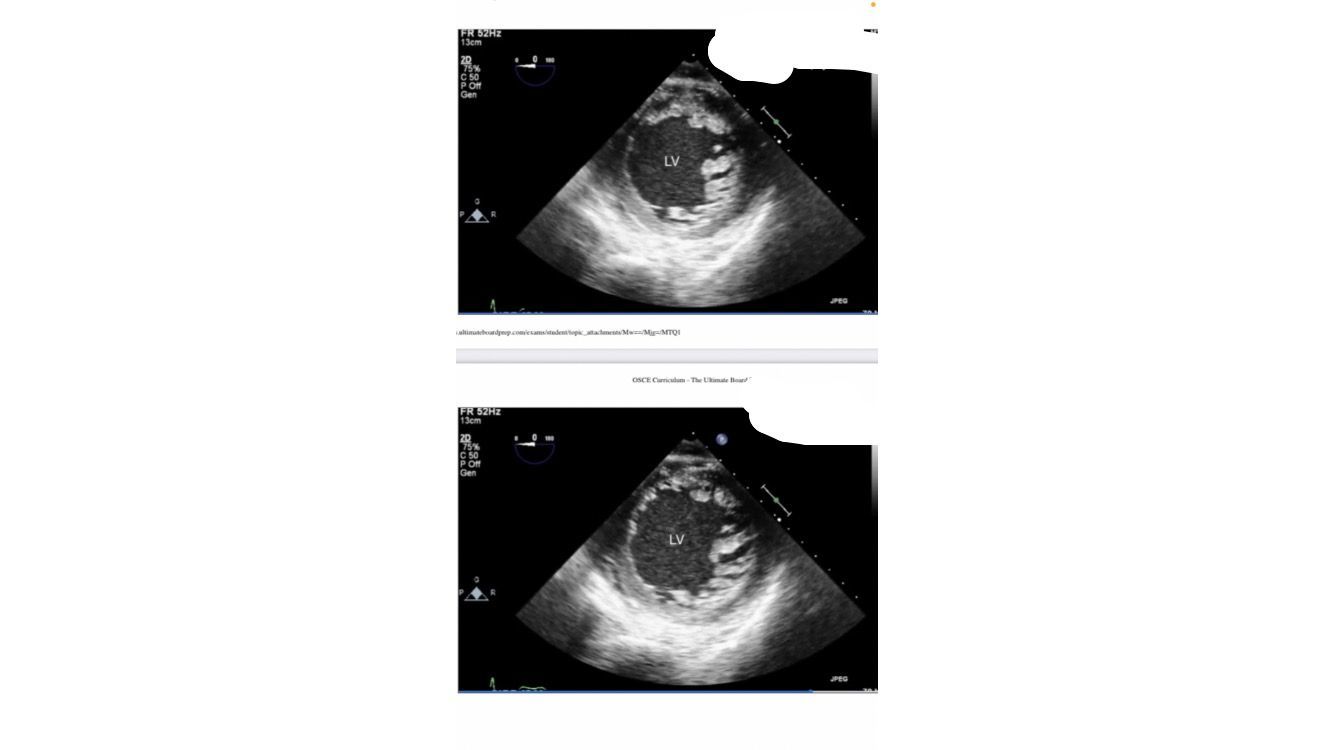

transgastric mid SAX view

systole and disatole

hypovolemia, very little movement/filling